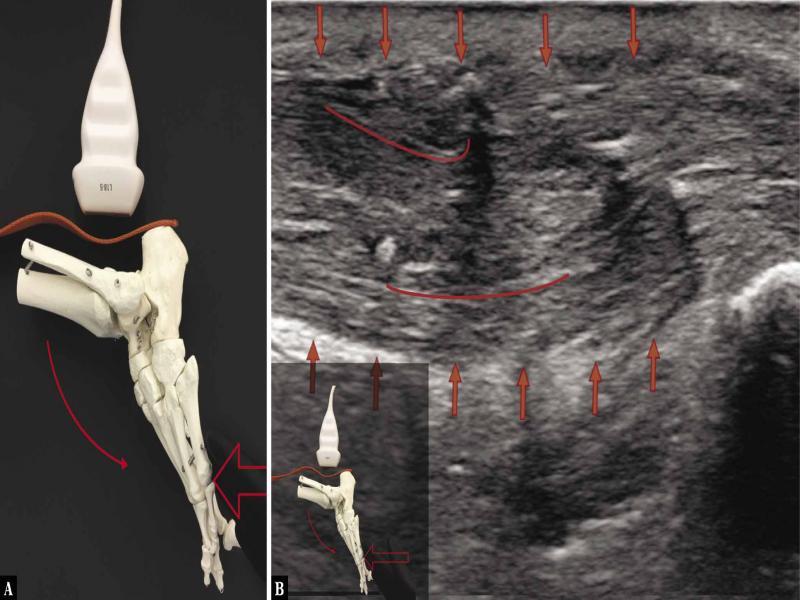

Fig. 4.

![Ultrasound examination protocol. A. The transducer is placed longitudinally above the calcaneal tuberosity, along the AT; active plantar flexion [curved arrow] of the ankle joint with the diagnostician’s hand applying ground-like foot resistance [straight arrow] as in the classical heel-rise test flexion. Evident tension of the AT. The heel-rise movement is made by the force of the triceps surae muscle with the tension of the AT. The image indicates a good function of a surgically treated AT. B. A longitudinal 18–5 MHz US image of the AT; evident fibrillar structure of the tendon fibres [red short lines]; good tendon tension; the image indicates a good function of the AT. [red arrows mark the borders of the tendon]](https://sciendo-parsed.s3.eu-central-1.amazonaws.com/64722e23215d2f6c89dbec00/j_jou.2021.0043_fig_005.jpg?X-Amz-Algorithm=AWS4-HMAC-SHA256&X-Amz-Content-Sha256=UNSIGNED-PAYLOAD&X-Amz-Credential=ASIA6AP2G7AKBY2AOJTK%2F20251216%2Feu-central-1%2Fs3%2Faws4_request&X-Amz-Date=20251216T170210Z&X-Amz-Expires=3600&X-Amz-Security-Token=IQoJb3JpZ2luX2VjEJ%2F%2F%2F%2F%2F%2F%2F%2F%2F%2F%2FwEaDGV1LWNlbnRyYWwtMSJIMEYCIQDpGWJy5nYmL6vQIHHt%2BcL%2F3OSMUmRuP2Jq%2F0ZR1%2FLQBwIhAMOCdMyV4r3yYa%2BF%2FudRVaQIR4fmJylEiwzwqN7lTdT5KrwFCGgQAhoMOTYzMTM0Mjg5OTQwIgz4VpTpHrGQ%2BRwhfVIqmQUmdJgnr7B%2F2TCxvDKqjEoGFRsgxmY1WO7B2uHZlmD80cdU17oWnLhWozEmhOcl3%2FA2q7bDkKBAuPcFO1a7dNHauScY2SzHlX0kIwGWBTyagWuMSXxWSKl7tuRn79BzKKKgACwrvnuaElPejVfsbXCLbokYmV3F5d6L7ZvYrBqtQi69XC21CoAlb8Y6i6%2FgGjbHb96ZBwCqvP7cOXSUTpBBNcWXDb3SBoKgMOvVGHUg3rSkHFBWbeUJWEqFQuQLNZGIPzAiqdGcNpaQoxwYfz5gf2hRAObi1TmBBQCJk0SxpwaFBWoacduWkTQZ5HNbLbV2Y7aFE3mDRSzYCiCfLMQh7Mgepw0nBxMmfE85hi32y%2BHl0YbHclUDfuc6cLW%2FYcTSrFNW5DY1zlMhrYkTdcHwhlV1hhIJTQNjAopybRxyhl8UYT%2FarnBEwsCeDtNSkjr%2BbyoA4Mb304CzPuGRdqK9emQVbV5UYjlPpV4HDHxB%2Feh%2FvM4JIZO4n8g6cp3NqtH4DmY0IW9MSRtklWQp1NGIx%2FvKjGOq7aOzqrJapYKvKLlD5e4RXY6v%2FiOPFbAdlTfn5%2FqC4BWLoxMGssJ9k0H38JHeskVYSwPhVqIo0EtaUeEaKSM06dRorQWA4zp9F2C8ovAo54ubZDzgUdOR0AQTvRjPzuFLiqLDfhn7QV8H0gLPqSM190VJgPIW5IZZPui4U7%2FBneLPSyQBM0j6QtUb8Mst%2FeYnWZLJMIdEPA%2Bv6au%2BzISiEhwEeyP69vVeq%2B5DRurxZDk6yvkPWt7OPS0VcMYYkMEE%2FBKpoOMCHV5smh95YG7YQar4J%2FuRfCRSBakAngbpy9rbUzTx0nincY30w2DOtdkRQ%2B6llm11f5dKO2lDvaYDR9zwsjDY3YXKBjqwAWriJvfX%2BElci0gwZQievDMAbkmHC4QI%2FqxewR1beknZpaCkRtCONkVDPkjy%2BT4qSFomaXZUpQZ4%2FUCmLMIxbgvXVx2C%2F8RvVqLErXggh0KomRU%2B0YjqHSFLW6f4wXhBudqG47DjGNdcJofTT2PytMHHltz%2Fhgs2cVWnTfkhMiVrxvUgXovn9cYHmefQfFeOjU7b7EZJzwNBhn624LDbKUNBrlDn2%2FKsMwkUHsc1t%2Flz&X-Amz-Signature=2aaeba683d1a0ec9b8f452013c52280528da71ec0bc19d68323e1290df9ab0f3&X-Amz-SignedHeaders=host&x-amz-checksum-mode=ENABLED&x-id=GetObject)